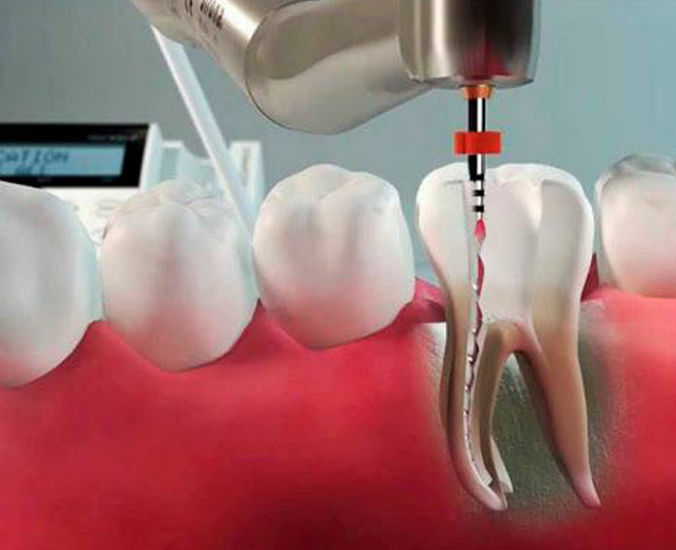

Tratamento de Canal

Tratamento de canal em dentes unirradiculares, birradiculares e multirradiculares.